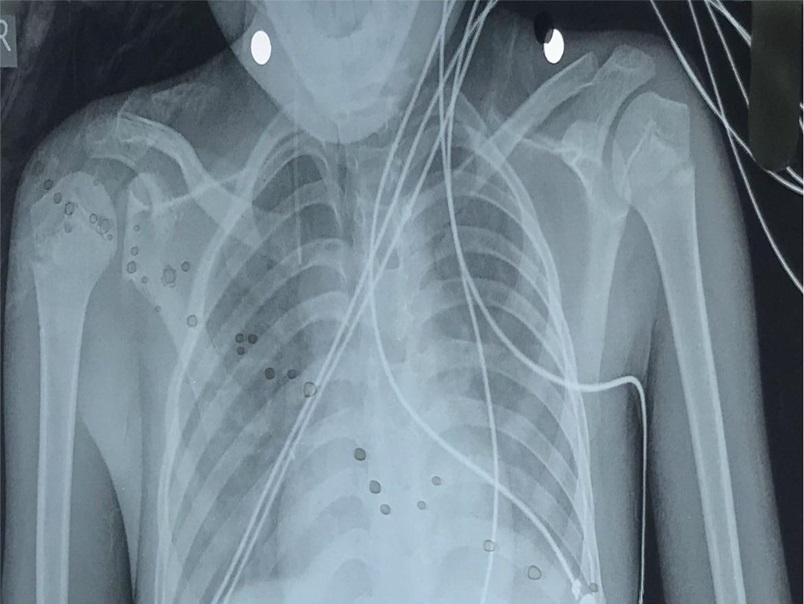

A 12-year-old patient, Aashiq, who entered our hospital in a disoriented state, showing a complex medical condition marked by acute complaints of insidious fever, abdominal pain, altered level of consciousness, inability to speak properly, abnormal b